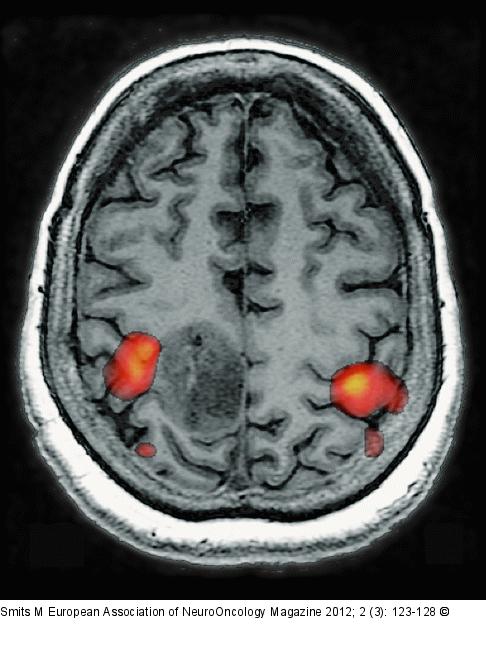

Figure/Graphic 1: Brain tumour Brain tumour localised in the primary hand motor cortex as evidenced by fMRI activation of a bilateral finger tapping task adjacent to the tumour in the precentral and post-central cortex bilaterally. |

Brain tumour localised in the primary hand motor cortex as evidenced by fMRI activation of a bilateral finger tapping task adjacent to the tumour in the precentral and post-central cortex bilaterally. |